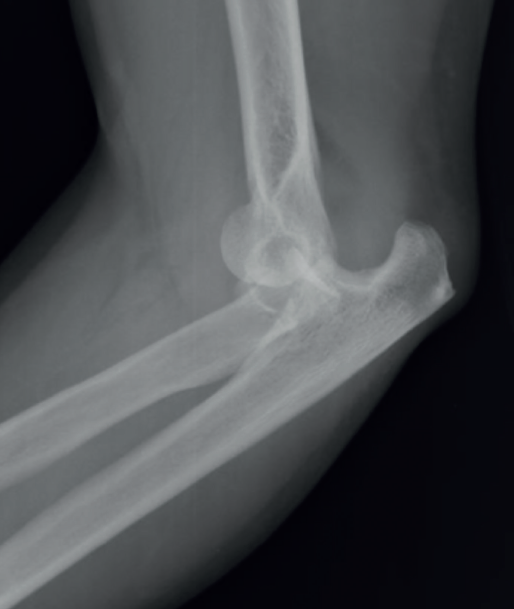

Finalmente, existen las lesiones que se producen por un trauma de alta energía contra el codo en flexión. Se genera una fractura-luxación transolecraneana, que puede conllevar una luxación anterior o posterior de codo.

Este tipo de lesiones se puede confundir con una fractura-luxación de Monteggia-Bado I. La diferencia es que no se ve afectada la articulación radiocubital proximal y los ligamentos colaterales medial y lateral permanecen anclados al fragmento distal del cúbito (Figuras 1, 2 y 3).